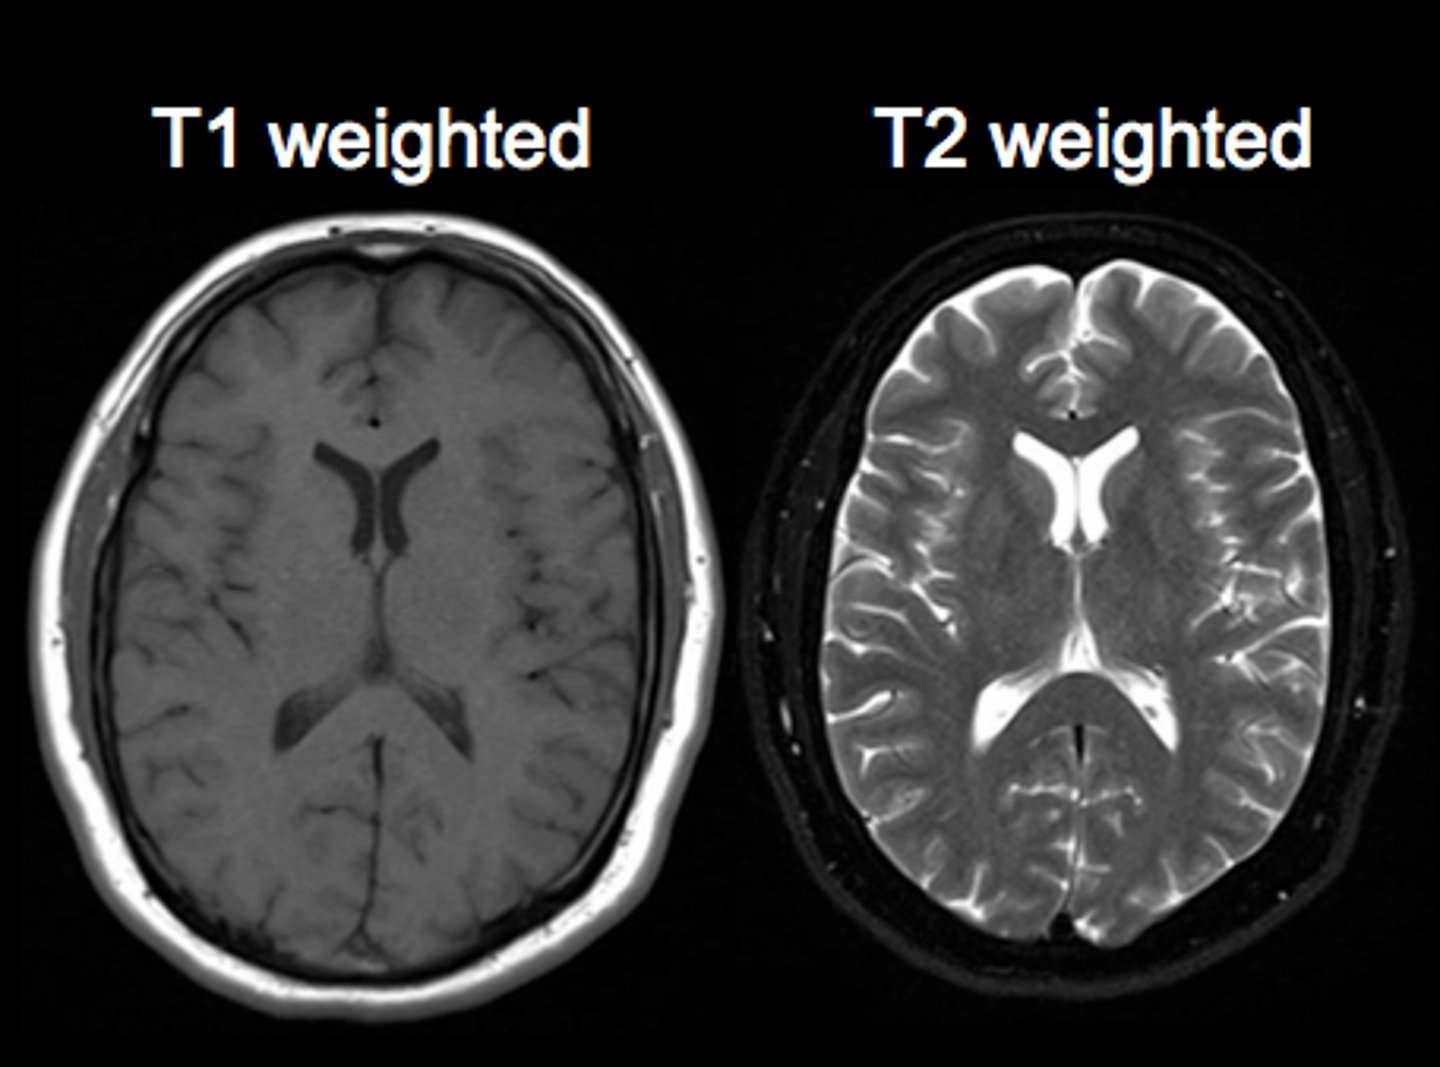

MRI T1 images

<p>Fat is white </p><p>Water is dark</p>

MRI T2 images

<p>Fat is dark</p><p>Water is white</p>